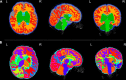

The Developing Human Connectome Project has created a large open science resource which provides researchers with data for investigating typical and atypical brain development across the perinatal period. It has collected 1228 multimodal magnetic resonance imaging (MRI) brain datasets from 1173 fetal and/or neonatal participants, together with collateral demographic, clinical, family, neurocognitive and genomic data from 1173 participants, together with collateral demographic, clinical, family, neurocognitive and genomic data. All subjects were studied in utero and/or soon after birth on a single MRI scanner using specially developed scanning sequences which included novel motion-tolerant imaging methods. Imaging data are complemented by rich demographic, clinical, neurodevelopmental, and genomic information. The project is now releasing a large set of neonatal data; fetal data will be described and released separately. This release includes scans from 783 infants of whom: 583 were healthy infants born at term; as well as preterm infants; and infants at high risk of atypical neurocognitive development. Many infants were imaged more than once to provide longitudinal data, and the total number of datasets being released is 887. We now describe the dHCP image acquisition and processing protocols, summarize the available imaging and collateral data, and provide information on how the data can be accessed.